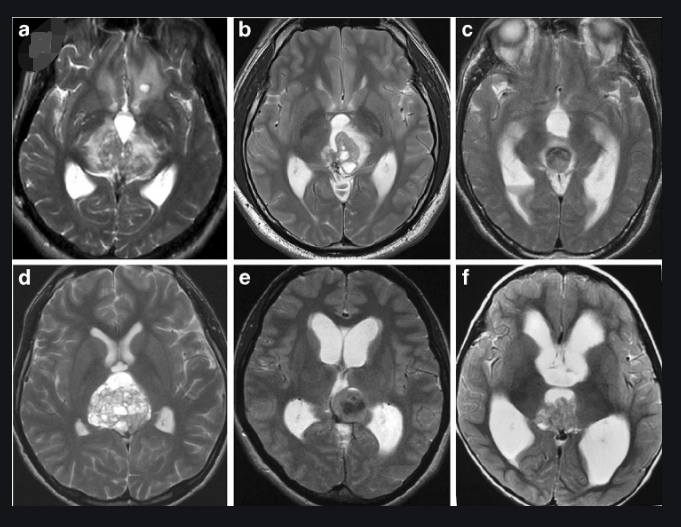

图片来源:https://en.wikipedia.org/wiki/Papillary_tumors_of_the_pineal_region

松果体区其他少见但值得注意的肿瘤包括发育性囊肿(表皮样囊肿)、松果体区乳头状肿瘤(PTPR)和胶质肿瘤(星形细胞瘤)。当这些松果体区肿瘤生长时,它们会压缩或侵入周围的大脑结构,导致各种神经功能缺陷。由于它们位于大脑中充满液体的区域,即脑室,它们也会导致因脑积水而增加的液体积累和颅内压。这些病变可以从良性囊肿到恶性肿瘤。